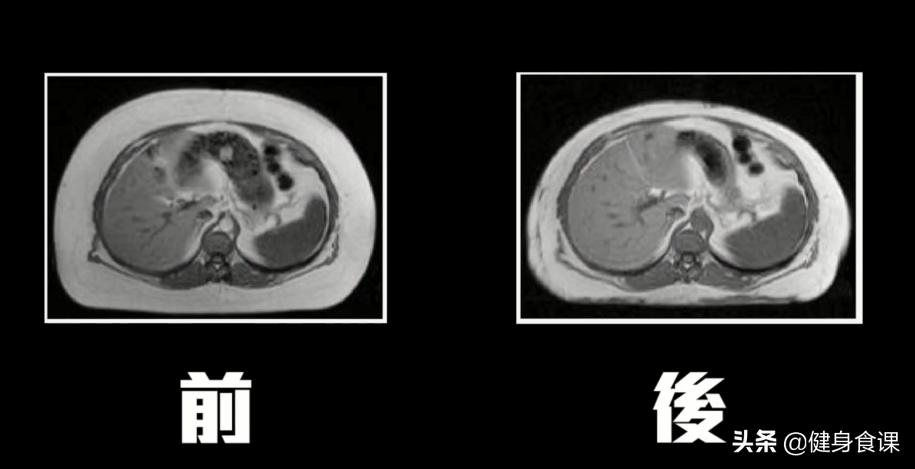

手术非常成功,他们平均抽掉了九到十公斤不等的脂肪,腰围整个小了一寸。

腹部的核磁共振也可以看出来:皮下脂肪从人本厚厚一圈变成比较薄一些手术本身非常的成功。

那么这些女生的健康状况有没有改善呢?结果他们的血压,血糖,空腹胰岛素、血脂肪、发炎指数的这些对心血管健康来说非常重要的指数竟然通通没有改变!原本就有糖尿病的人抽了一堆脂肪掉,结果血糖也还是一样高。